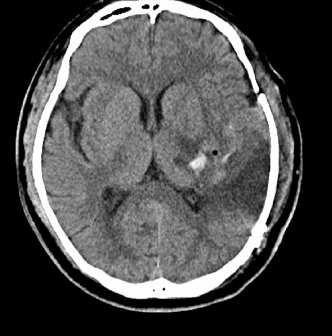

很快 , 护工推着平车 , 在医生护士的陪同下 , 完成了对这个病人的急诊头颅CT检查 。

文章图片

CT的影像让大家一惊 , 脑出血 ,巨大的血肿已经造成了中线的移位、一侧侧脑室的受压 。